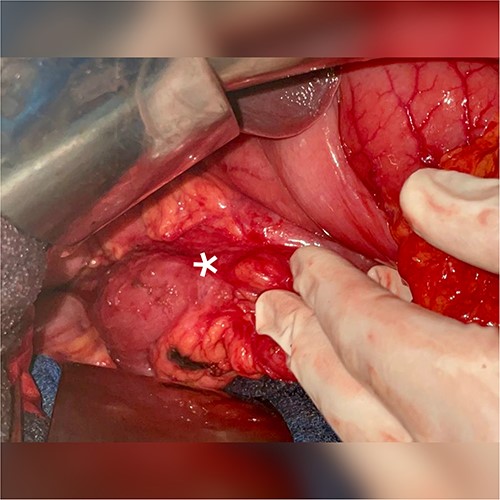

A 51-year-old patient with no significant medical history. He was admitted to the emergency department with abdominal distension, persistent vomiting, intolerance to solid foods, he could consume only small amounts of liquid. Clinical examination of the abdomen revealed diffuse tenderness in all quadrants, accompanied by severe abdominal distension. Prior to his consultation at our institution, he had undergone oesophagogastroduodenoscopy, revealing a dilated stomach and narrowing of the pyloric ring. Biopsies revealed the presence of H. pylori and S. ventriculi. (Fig. 1). He was put on conservative treatment for a duration of ~4 weeks, but no significant improvement was noted. On admission to our clinic, he underwent a computed tomography (CT) scan of the abdomen (Fig. 2), which revealed marked dilatation of the stomach, as well as an upright arrangement of the entire jejunal coves, suggesting the presence of a high occlusion due to a right anterior para-duodenal internal hernia. While a more comprehensive non-operative management approach could have been contemplated in the absence of hernia-related concerns, the clinical deterioration and the refractory nature of symptoms to medical therapy served to underscore the appropriateness of the surgical approach. During surgery, the hypothesis of a para-duodenal internal hernia was ruled out after a duodeno-pancreatic detachment using the KOCHER maneuver, thus facilitating exposure of the entire duodenum and also allowing individualization of the transition zone located at the level of the pylorus (Fig. 3), thus justifying the performance of gastroenteric anastomosis (Fig. 4). Post-operatively, the diet was progressively advanced and well tolerated. On discharge, the patient was in satisfactory condition.

CT scan of the abdomen, which revealed marked dilatation of the stomach.